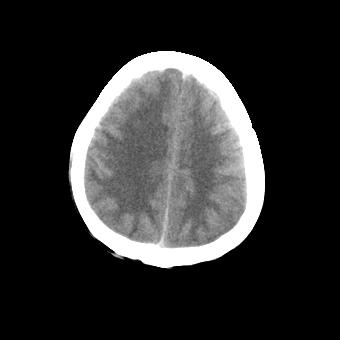

标题: CT16478:男 头晕 恶心 呕吐 [打印本页]

标题: CT16478:男 头晕 恶心 呕吐

病人不合作,图像质量差,右额叶及后纵裂可见高密度影,建议复查。

图像不好看,暂时考虑脑水肿,稳当起见建议复查

伪影太多,不好诊断

没有提供病史,图像质量又差,很难做诊断。

[quote]以下是引用叶子123在2008-11-13 9:55:00的发言:[br]患者因煤气中毒入院,临床及ct均诊断一氧化碳中毒性脑病[br][br]